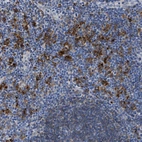

Immunohistochemistry analysis in human lymph node and cerebral cortex tissues using Anti-HLA-DPA1 antibody. Corresponding HLA-DPA1 RNA-seq data are presented for the same tissues.